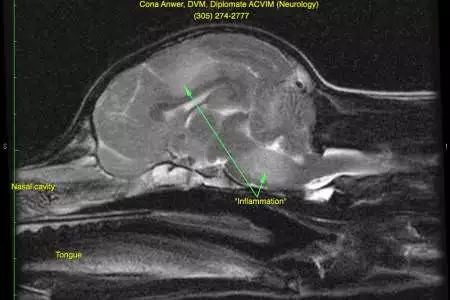

Based on Charlie’s examination, a problem affecting the left front part of the brain (cerebral cortex) was suspect. Magnetic resonance imaging (MRI) was performed. The first image is of Charlie’s head in profile. The nose is toward the left and the top of the head is toward the top of the picture. The second image is made 90 degrees to the other image as if Charlie’s nose was coming out of the computer screen. The right side of the picture is the left side of Charlie’s head. The brain is in the middle of the picture. The bright areas within the brain (arrows) represent inflammation, also called encephalitis.

Charlie scan